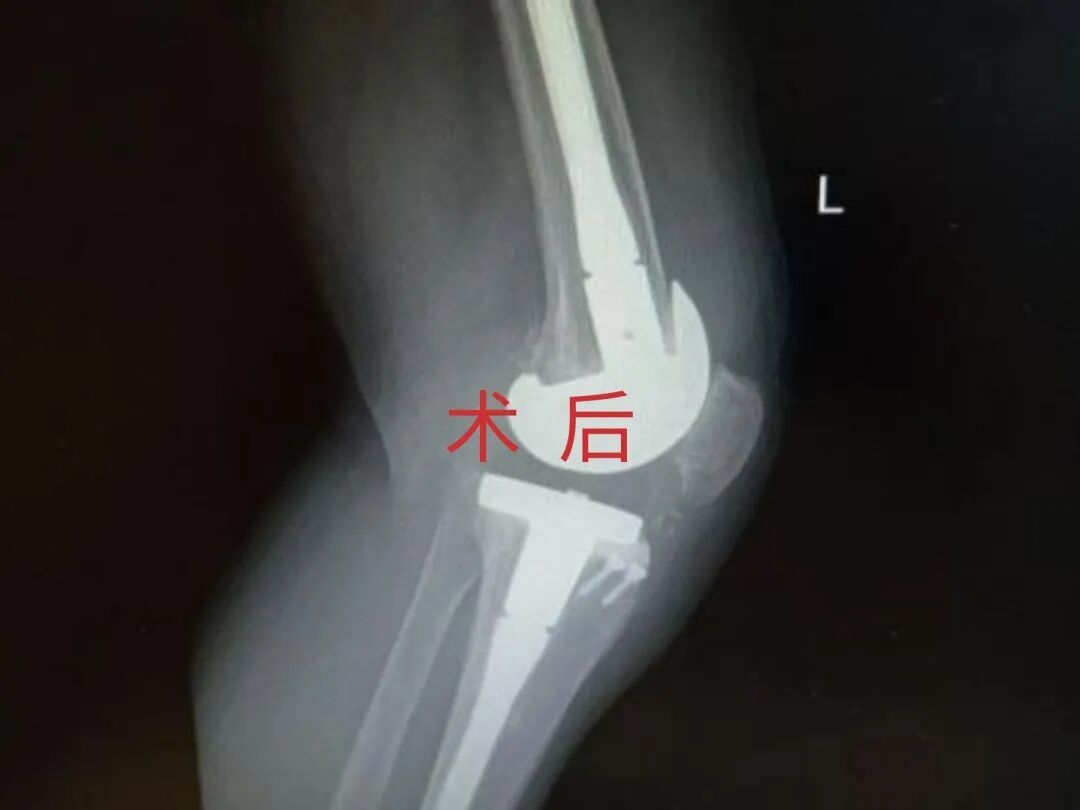

为提升区域内基层医疗机构糖尿病足诊疗服务能力、促进青年医师对糖尿病足的规范化诊治水平,遵义市第二城市医疗集团总院(贵州航天医院)圆满举办贵州省继续医学教育项目——胫骨横向骨搬移技术治疗糖尿病足专题研讨班。 贵州航天医院党委委员、副院长彭亮出席会议并致辞,遵义市第二城市医疗集团各成员单位,以及红花岗区、汇川区、绥阳县、桐梓县等多个区县的基层医疗机构骨干医师参加会议。 研讨班 本次研讨班以胫骨横向骨搬移技术在糖尿病足治疗中的应用为核心主题,围绕糖尿病药物治疗与生活方式管理策略、围手术期血糖精准调控要点、胫骨横向骨搬移技术典型病例深度解析、糖尿病足的临床分型与个体化治疗方案制定等临床实践中的热点与难点展开深入探讨,通过专题授课、案例研讨、互动交流等多元化形式,为参会者搭建了理论与实践结合的学习平台。 此次研讨班不仅为区域内基层医院搭建了学术交流与经验共享的平台,更对推动糖尿病足预防、诊断与治疗的规范化、系统化发展起到了积极作用,有效助力青年医师更新专业知识体系、提升临床技能,为进一步保障区域内糖尿病足患者的健康奠定了坚实基础。 贵州航天医院骨科专家简介 陈明勇 骨一科主任,副主任医师 临床擅长:从事创伤骨科工作约20年,对骨缺损、骨不连、骨肿瘤、肢体畸形等的肢体矫形重建及功能重建,慢性化脓性骨髓炎的根治治疗、糖尿病足的保肢治疗、快速康复理念(ERAS)下的老年骨折的诊治,四肢复杂骨折的诊治,四肢骨折等微创手术治疗具有丰富的临床经验。 2004年毕业于遵义医学院临床专业,曾在中国人民解放军总医院、广西医科大学第一附属医院、上海第六人民医院骨科进修。中国中西医结合学会骨伤科专业委员会横向骨搬移治疗糖尿病足及微血管网再生学组首届委员,遵义市医学会创伤分会常务委员。 瞿 晖 骨科党支部书记,骨二科主任,副主任医师 临床擅长:对骨科的常见病、关节外科、脊柱外科及运动医学疾病的诊治具有丰富的临床经验,熟练掌握骨科手术操作技术。 毕业于遵义医学院临床医学系,2005年前往广州中山大学第一附院骨显微医学部进修学习,2011年前往成都华西医院进修学习,并多次在省内外学习骨科相关知识,是中华医学会骨科分会会员。 赵小锋 中共党员,骨二科副主任,副主任医师 临床擅长:从事骨科临床工作11年,对骨科常见病、多发病诊疗有较为丰富的临床经验,擅长脊柱相关疾病诊断及治疗,尤其是颈、腰、腿疼痛疾病诊断及治疗,擅长胸腰椎骨折微创经皮穿刺内固定术、经皮穿刺椎体成形术、经皮穿刺脊柱内镜下腰椎间盘摘除术、单纯开创腰椎间盘摘除术、腰椎滑脱复位椎间植骨椎融合内固定术、腰椎管狭窄减压融合内固定术及人工髋、膝关节置换术等。 2012年毕业于遵义医学院外科学专业硕士研究生,2019年参加“遵义市115医学人才精英计划”于上海交通大学第一附属医院培训学习,2023年于北京大学第三人民医院脊柱外科进修学习,曾获得遵义市优秀医师荣誉称号。 遵义市手外科第一届委员,遵义市医学会创伤分会第一届委员,遵义市医学会创伤分会第二届委员,贵州省康复医学会第三届脊柱脊髓专业会委员,遵义市医学会烧伤与整形外科学分会委员,发表论文5篇,其中国家级核心期刊1篇,SCI论文1篇,主持市级课题1项并结题,参与市级课题2项。 赵兴东 骨科主任医师 临床擅长:擅长骨科的常见病及各种创伤、四肢骨折创伤修复、骨感染、手足疾病的诊治和手足体表畸形的矫形整复,熟练掌握骨科四肢骨病及创伤的手术操作技术,尤其在四肢关节复杂性损伤、手足外伤、组织缺损创面、难治创面的皮瓣修复方面及平足、高弓足矫形方面及四肢慢性疼痛诊治、康复方面具有丰富的临床经验。 硕士研究生,毕业于遵义医学院临床外科系,2015年前往山东省立医院手足外科进修学习;遵义市医学分会创伤分会第一、二届委员,遵义市手外科医学会第二委届员会常务委员;在省级及省级以上期刊发表文章9篇,参编著作2部,参与主持并完成市级课题1项,参与市级课题2项、省级课题1项。 张艳金 中共党员,骨科副主任医师 临床擅长:从事骨外科工作16年,对复合伤、多发伤的救治、四肢骨干骨折、关节周围骨折、骨肿瘤、骨髓炎等诊治具有丰富的临床经验。 中共党员,硕士研究生,2006年本科毕业于山西医科大学第二临床医学院,2011年研究生毕业于北京军区总医院;在“老年COPD患者合并髋部骨折的诊治”国际合作课题组研究两年,在老年髋部骨折的诊治方面具有丰富的经验,并发表论文6篇;主持遵义市级课题1项,承担遵义医科大学的临床教学工作,获得遵义医科大学优秀带教老师荣誉。编撰有《骨科疾病诊疗精粹》一书,开展2项新技术,编撰地方规范《务川自治县创伤骨科常见疾病诊疗规范》一书。 张俊凯 骨科副主任医师 临床擅长:从事骨科临床工作28年,对创伤骨折、骨感染、骨缺损、骨不连等外科诊治,四肢骨折的微创手术治疗,四肢复杂骨折(如关节内粉碎性骨折、多发骨折等)的损伤控制及手术治疗等具有丰富的临床经验。 1995年毕业于遵义医学院临床专业,2009年前往复旦大学附属医院骨科进修1年。 卢懿明 中共党员,骨科副主任医师 临床擅长:从事骨科工作18年,对创伤骨折、四肢骨折的微创手术治疗、四肢复杂骨折(如关节内粉碎性骨折、多发骨折等)的损伤控制及手术治疗,尤其是髋部骨折的PFNA等微创技术,踝关节骨折、膝关节周围骨折的Mipo微创技术等具有丰富的临床经验,开展了4项新技术,发明6项新型专利技术。 2005年毕业于遵义医学院临床专业,2017年,前往南方医科大学第三附属医院骨科进修半年,回院后运用Mipo技术对骨干骨折及干骺端骨折的治疗技术,同时积极开展骨盆骨折、髋臼骨折腹直肌外侧切口的应用;发表了多篇专业论文,经常参与省内外学术交流会授课,获得医院荣誉称号多个。 邬夏荣 骨科副主任医师 临床擅长:从事骨科工作16年,对四肢复杂骨折、骨肿瘤的诊治,尤其是足踝创伤、慢性踝关节损伤、平足症等诊疗具有丰富的临床经验。 2006年毕业于遵义医科大学临床医学专业,曾在陆军军医大学西南医院进修学习,发表多篇骨科学术论文。 余德怀 中共党员,骨科副主任医师 临床擅长:从事骨科工作10余年,对运动医学、骨关节、脊柱外科常见病、多发病的诊治具有丰富的临床经验。 硕士研究生,2011年毕业于遵义医学院临床医学专业,曾前往遵义医科大学附属医院运动医学专业进修学习;是贵州省医学会运动医学分会青年委员,西部关节镜联盟委员;发表多篇骨科学术论文。 冯 乾 骨科副主任医师 临床擅长:从事骨科工作近20年,熟练掌握骨科多发病及常见病的诊治,尤其对脊柱退变性疾病的诊断及治疗具有丰富的临床经验,主要研究脊柱微创相关治疗方式,能熟练开展椎间孔镜及UBE。 曾前往北京大学第三医院进修学习疼痛及椎间孔镜、首都医科大学友谊医院专业进修脊柱内镜;是贵州省康复医学会第三届脊柱脊髓专业委员会委员;发明专利3项、发表脊柱外科专业论文多篇。 贵州航天医院骨科简介 基本情况 贵州航天医院(原3417医院)骨科组建于1968年,前身是以创伤和断肢(断指)再植闻名于世的上海市第六人民医院骨科,中国断肢(断指)再植的奠基者、中科院院士陈仲伟等专家莅临科室指导医疗和教学,并在70年代开展了贵州省首例断肢(断指)再植手术。组建50余年来,诊治患者已逾百万,挽救了无数的伤病员,成为了保障遵义地区人民群众健康的重要支撑。 经过几代人的不懈努力,今天的骨科,已由创伤骨科发展至骨病、骨肿瘤、骨结核等领域,现有脊柱外科、关节外科、四肢创伤、手足外科四个亚专科,成为了集医疗、教学、科研于一体的综合学科,是贵州省临床重点专科、遵义市临床重点专科、遵义市骨科临床医学中心、遵义市基层骨科专科联盟理事长单位。 科室目前开放床位110张,共有医护人员50余人,副高级以上专家18人,硕士研究生15人。拥有一流骨科医疗设备多台,每年不定期选派优秀技术骨干到全国各大知名医学院校进修、学习、参观、交流,并邀请国内、国外知名专家教授来院进行交流、指导,通过不断引进国内外先进的诊疗技术,科室医疗技术水平稳步提升,为广大人民群众提供了优质的医疗服务。 专科特色 骨一科 (一)骨缺损、骨不连的肢体与功能重建 胫骨横向骨搬移技术治疗糖尿病足: (二)慢性骨髓炎的根治治疗 (三)肢体缺血性疾病如糖尿病足、脉管炎的保肢治疗 (四)皮瓣修复 (五)复杂创伤的治疗 (六)老年髋部骨折及小儿骨折快速手术 老年髋部骨折: 骨二科 (一)胸腰椎骨折微创经皮椎弓根螺钉固定术 (二)老年性骨质疏松性患者腰椎滑脱脊柱内固定术(骨水泥螺钉) (三)V形双通道脊柱内镜技术(VBE)腰椎融合术治疗腰椎退行性疾病 (四)老年性骨质疏松性骨折(PVP/PKP)术 (五)人工髋关节置换术 (六)双侧股骨头坏死人工全髋关节置换 (七)右侧全髋置换术后假体周围骨折翻修 (八)人工膝关节置换术 (九)人工膝关节假体松动翻修 (十)关节镜技术 传统手术切口 关节镜技术切口 诊疗范围 骨一科 1.四肢创伤、矫形。 2.手、足踝外科。 骨二科 End